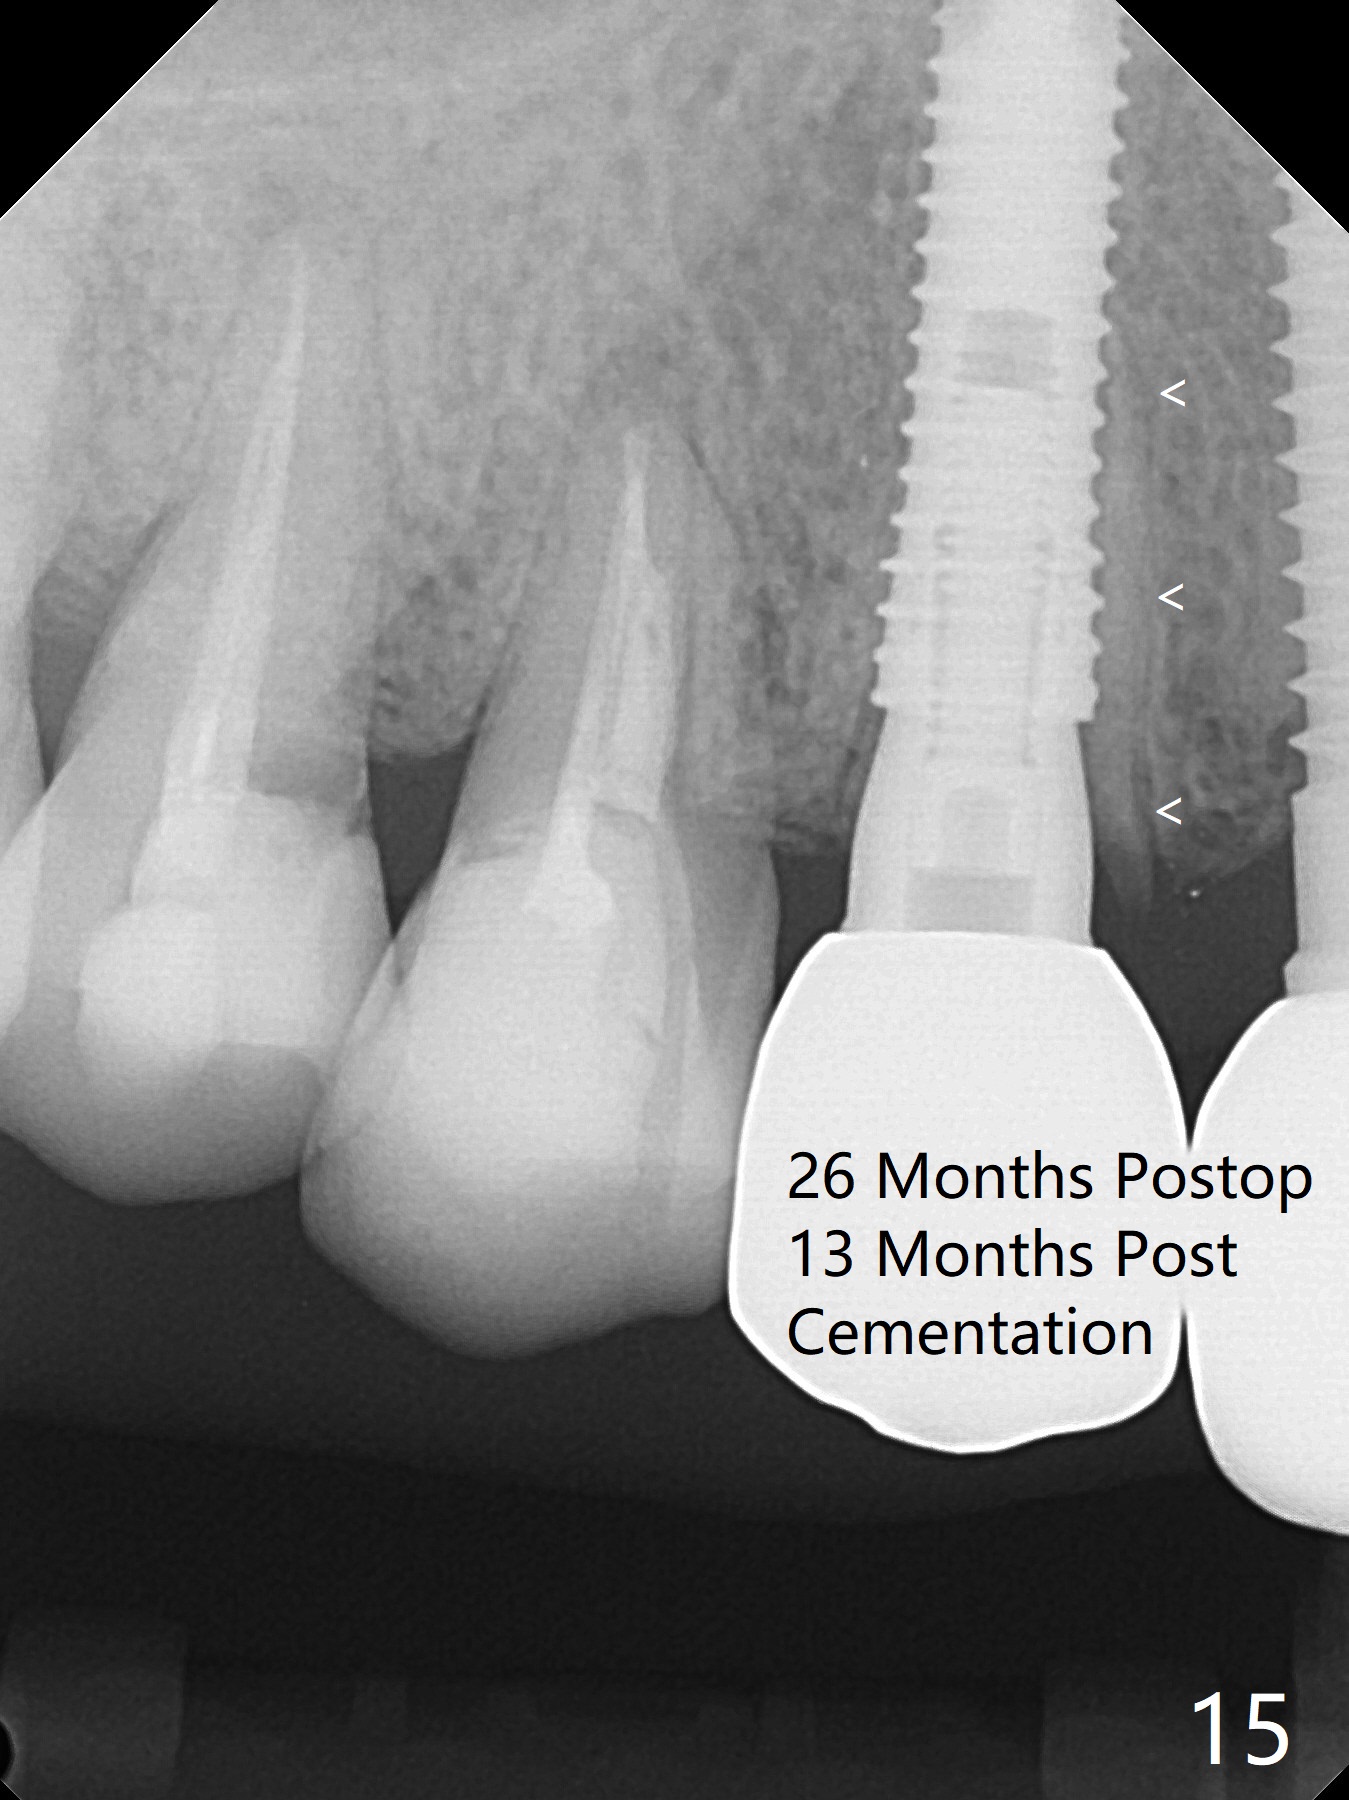

Since the ridge at #7 is ~ 4 mm, a 2.5x14 mm 1-piece implant is placed (Fig.8) after 1.2 mm (Fig.7), and 1.5 mm drills at 12 mm and 2 mm drill at 8 mm.  Later the implant is placed deeper (Fig.10).  There is no bone loss 7 or 12 months postop, respectively (Fig.11,12).  After Diode gingivectomy, there is papillary formation (Fig.13).  No provisional is provided after impression (with the abutment torqued at #6) for oral hygiene.  With access holes at #6 and 7, crowns are bonded with minimal residual cement (Fig.14 <, which is removed later).  There is no hard (Fig.15,16) or soft (Fig.17 *) atrophy 26 months postop, i.e., 13 months post cementation, due to the presence of socket shield (Fig.15 <, as compared to Fig.1).  In fact the tooth #8 has mobility and fremitus (short root/poor crown/root ratio, Fig.16); occlusal adjustment is done 13 months post cementation.  The crown is dislodged 2 years 1 month post cementation; a prefabricated post is being tried in (Fig.18).  There is no atrophy, bone loss or infection at #6 (with socket sheath (*)) or 7 two years 5 months post cementation (Fig.20-27).